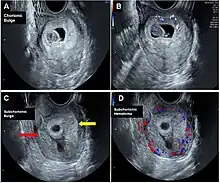

Chorionic bump is a rare medical condition defined as an irregular, convex bulge or protrusion from the choriodecidual surface into the gestational sac.[1][2] It is medically defined as a separate entity from a chorionic hematoma.[3]

It is believed that chorionic bump can start as a hematoma in the intervillous space.[5] Additionally, Infertility treatments may be associated with increased likelihood of chorionic bump.[4]